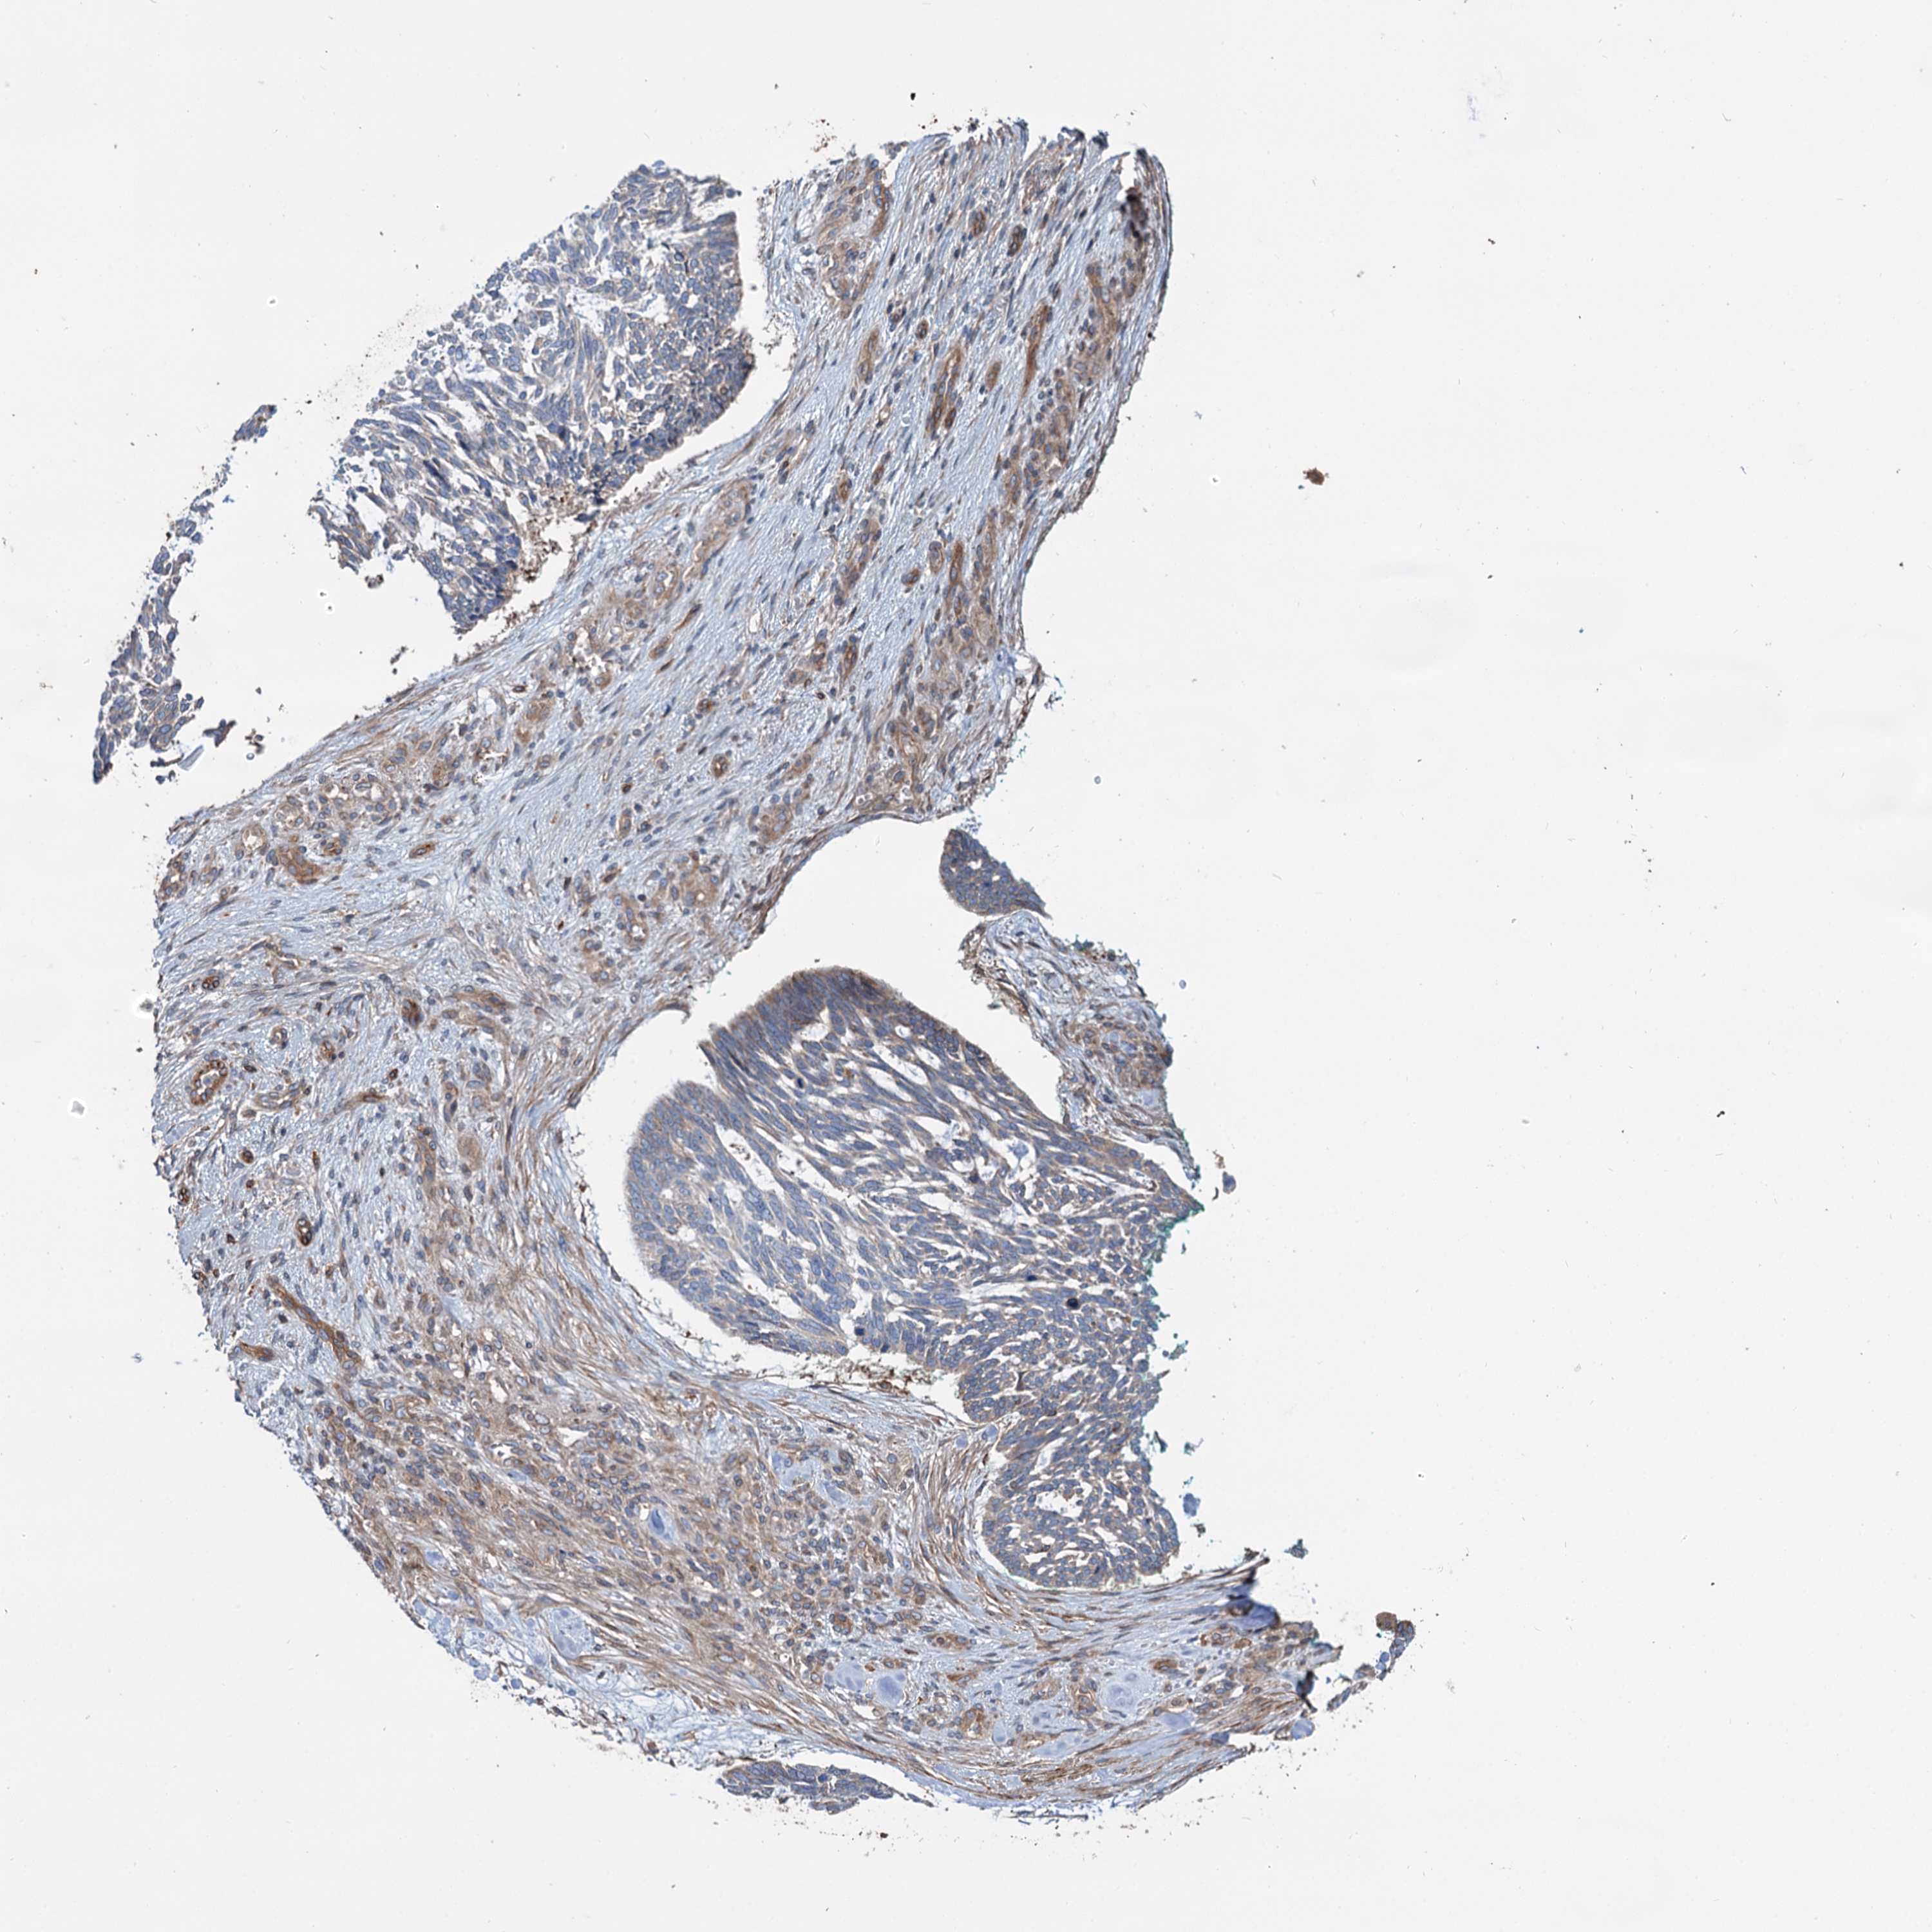

SKIN CANCER - Protein expressioni

A mouse-over function shows sample information and annotation data. Click on an image to view it in a full screen mode. Samples can be filtered based on level of antibody staining by selecting one or several of the following categories: high, medium, low and not detected. The assay and annotation is described here.

Antibody stainingi

Antibody staining in the annotated cell types in the current human tissue is reported as not detected, low, medium, or high, based on conventional immunohistochemistry profiling in selected tissues. This score is based on the combination of the staining intensity and fraction of stained cells.

Each image is clickable and will lead to virtual microscopy that enables deeper exploration of all samples and also displays staining intensity scores, fraction scores and subcellular localization as well as patient and tissue information for each sample.

Antibody HPA038928

Basal cell carcinoma